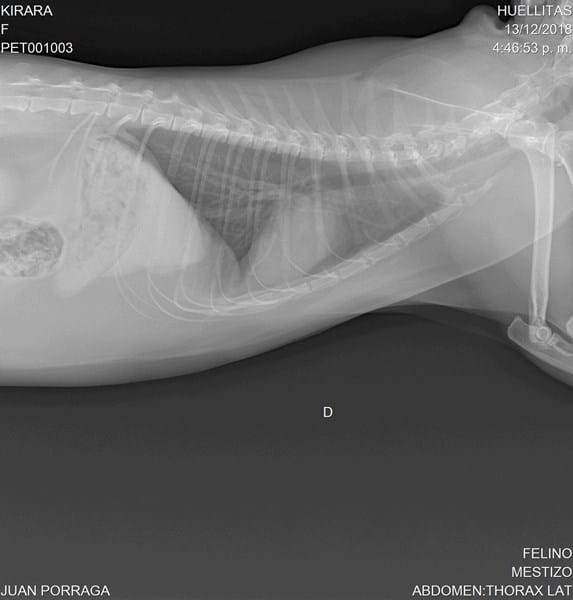

Mi gata de 4 años, castrada, presenta ruidos al respirar (no es permanente solo en ocasiones) donde parece pujar o generar silbidos (sobre todo al ronronear). También presenta estornudos ocasionales, ronquidos en raras ocasiones y tos muy de vez en cuando. Se le ha realizado una radiografía de tórax y demás y sale en completa normalidad (pulmones y vías respiratorias), la veterinaria dice que puede ser por estar un poquito pasada de peso, pero los ruidos continúan y me siento preocupado.